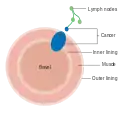

Dukes stage B bowel cancer; the cancer has invaded the muscle. Dukes stage C bowel cancer; the cancer has invaded the nearby lymph nodes.

Dukes stage C bowel cancer; the cancer has invaded the nearby lymph nodes. Dukes stage D bowel cancer; the cancer has metastasized.

Dukes stage D bowel cancer; the cancer has metastasized.